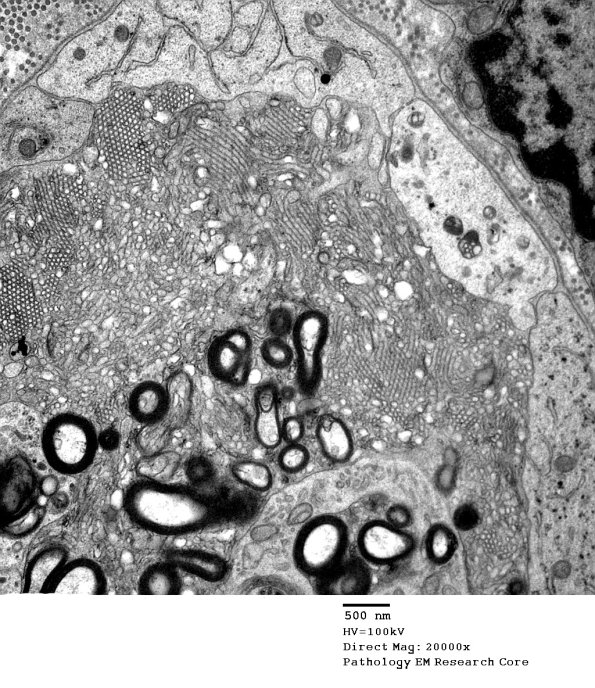

Washington University Experience | PERIPHERAL NEUROPATHY | 4 AXONAL DEGENERATION | 3 Electron Microscopy | 2G4 Axonal Degeneration (Case 7) EM 019A - Copy

In this region there are vesicular myelin changes and adjacent Schwann cell processes which may resemble axons. Ribosomes in Schwann cell processes often give a hint they are not axons.